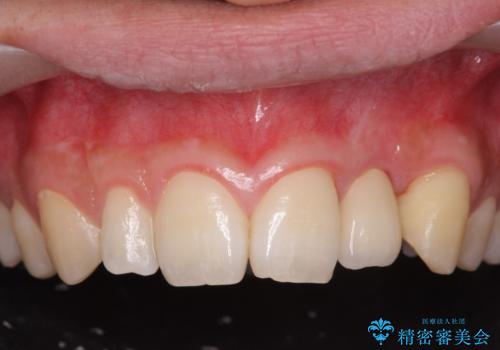

- 前歯の永久歯が元々なく、乳歯を失ったタイミングで前歯の審美性の回復を求めて来院されました。

機能・審美性の回復手段として、インプラント治療・ブリッジ・部分床義歯が考えられます。

それぞれの治療に特徴がありますが、取り外しの必要がなく隣の歯を削る必要も必要ないインプラント治療を選択されました。

- 55万円(ストローマンインプラント・ジルコニアカスタムアバットメント・骨造成・仮歯・ジルコニアクラウン)費用は治療当時の料金となります

前歯部にインプラントを埋入し、きれいに仕上げるためには骨の造成技術や歯肉の厚みを増すような処置を行い、インプラント周囲の環境を整備することが肝要です。